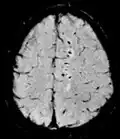

| Effective T2 or "T2-star" |

T2* | Spoiled gradient recalled echo (GRE) with a long echo time and small flip angle[74] | Low signal from hemosiderin deposits (pictured) and hemorrhages.[74] |

| |

| Susceptibility-weighted | SWI | Spoiled gradient recalled echo (GRE), fully flow compensated, long echo time, combines phase image with magnitude image[75] | Detecting small amounts of hemorrhage (diffuse axonal injury pictured) or calcium.[75] |